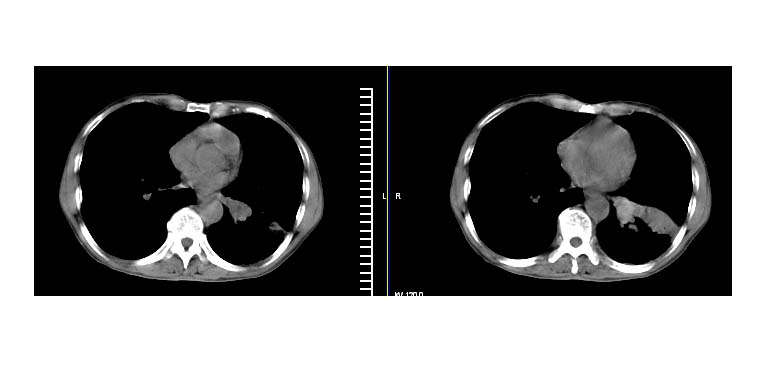

标题: CT11019:男性,66岁。发烧5-6天。治疗后无明显好转。 [打印本页]

标题: CT11019:男性,66岁。发烧5-6天。治疗后无明显好转。

阻塞性肺炎并不张,建议抗炎治疗后复查或增强

左下肺中心性肺癌伴下肺不张及周围阻塞性炎症

左下肺中央型肺癌伴阻塞性肺炎\\肺不张可能性大,建议支纤镜检查

左下肺中心性肺癌伴下肺不张及周围阻塞性炎症,

建议:支气管镜检查。

左肺门下分增大见有结节影,基底干及分支显示不清,下叶体积缩小,呈片带状机磨玻璃样影显示。支持考虑左下肺中心型肺癌伴阻塞性肺炎及部分肺不张。建议纤支镜检查